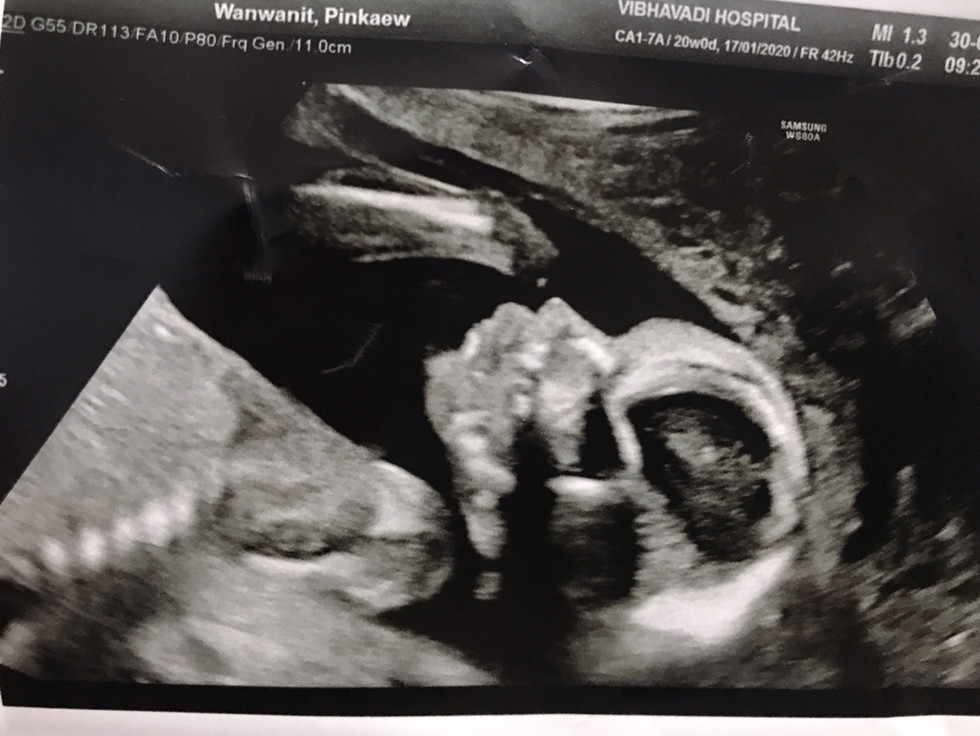

คุณหมอไม่รอหนูดิ้นเลยไม่รู้ว่าหญิงรึชาย😹